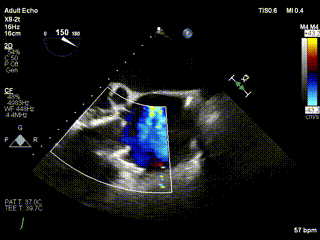

2021年12月24日,復(fù)旦大學(xué)附屬中山醫(yī)院葛均波院士團(tuán)隊(duì)成功應(yīng)用LuX-Valve Plus為一例極重度三尖瓣反流(TR)合并房顫、房缺的患者完成了經(jīng)血管三尖瓣置換術(shù),這是在前基礎(chǔ)上,本周完成的第三例經(jīng)血管三尖瓣置換手術(shù),葛均波院士、周達(dá)新教授等與心外科魏來(lái)教授、賴顥教授,心超室的潘翠珍教授、李偉教授及麻醉科的郭克芳教授共同完成了本周手術(shù),均獲得圓滿成功!患者術(shù)后超聲顯示無(wú)TR,臨床癥狀明顯改善。本周手術(shù)的成功也為L(zhǎng)uX-Valve Plus救治性臨床研究添上了濃墨重彩的一筆。

三例患者入院后,葛均波院士團(tuán)隊(duì)周達(dá)新教授、潘文志教授、張?jiān)床┦?、陳莎莎博士及心超室的潘翠珍教授、李偉教?/strong>對(duì)患者的情況進(jìn)行詳細(xì)評(píng)估和討論,最終決定為三例患者選擇LuX-Valve Plus40mm、50mm和50mm型號(hào)的瓣膜進(jìn)行手術(shù)治療。手術(shù)后即刻拔除氣管插管,術(shù)后患者三尖瓣反流癥狀得到顯著改善,復(fù)查心超結(jié)果顯示人工三尖瓣瓣膜支架固定穩(wěn)定,瓣葉關(guān)閉形態(tài)未見(jiàn)異常,未見(jiàn)明顯反流。